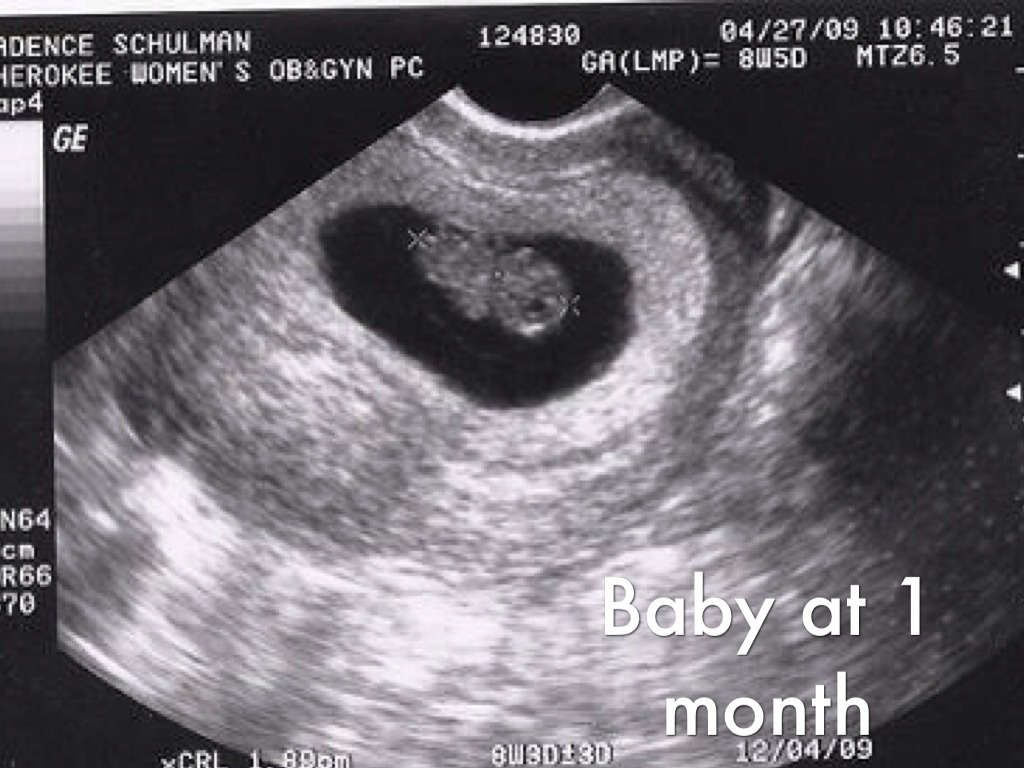

Baby at 1 month

The baby is a zygote,basically the baby is a grouping of the cells.